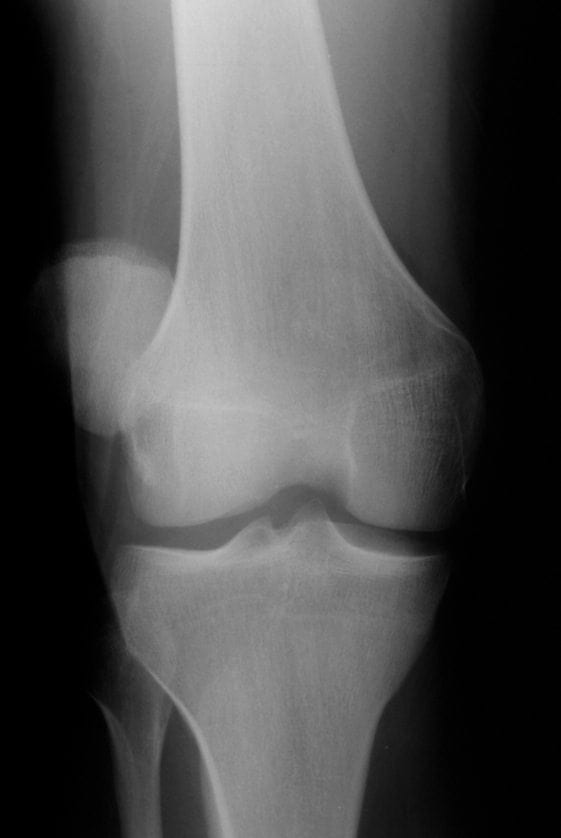

Patellofemoral Syndrome X Ray Floating Patella Disease Patellar (or kneecap) instability most commonly occurs in people in their teens and 20s. Many people with symptoms of kneecap pain are diagnosed with patella subluxation or maltracking of the patella. Patellar instability is a condition characterized by patellar subluxation or dislocation episodes as a result of injury, ligamentous laxity or increased q angle of the knee. When the kneecap. Floating Patella Disease.